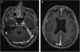

Tuberculosis of meninges

Tuberculous meningitis is also known as TB meningitis or tubercular meningitis. Tuberculous meningitis is Mycobacterium tuberculosis infection of the meninges—the system of membranes which envelop the central nervous system. [Source: Wikipedia ]